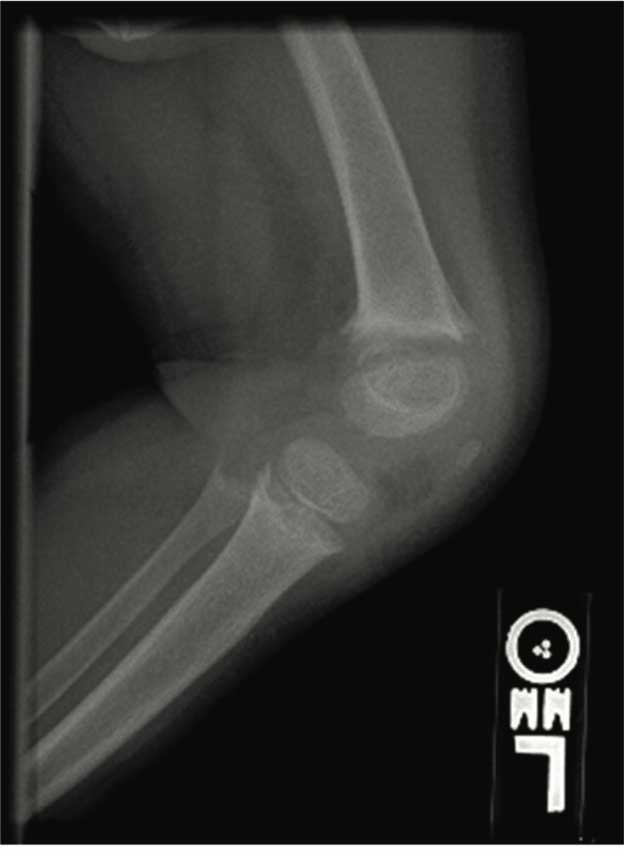

Radiographic studies of knee and wrist joints are showed in the upper figure. She was treated with ergocalciferol at various doses for 2 years with no improvement. Her serum 25 hydroxy vitamin D increased from 22 ng/mL at baseline to 80 ng/mL after a megadose of ergocalciferol. Repeat radiographs of her knees at age 3 years showed increased widening of epiphyses with increased cupping and fraying of the metaphyses (lower figure). She had complaints of polyuria, polydipsia, enuresis, and bone pain.